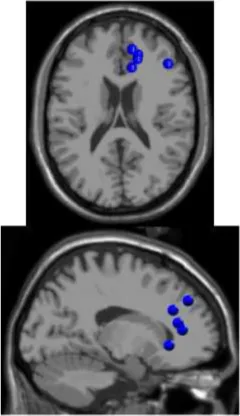

As expected the average treadmill belt velocity was more variable during active treadmill walking, regardless of command speed (Figure 3A). Average pelvis velocity in the sagittal plane was similar for the slow and fast walking commands, indicating the participants were able to match the desired treadmill command speed accurately during the steady walking tasks (Figure 3B). The k-means clustering resulted in seven spatially distinct clusters of electrocortical dipole sources, plus one additional outlier cluster (Table 1). We identified the Brodmann areas represented within each cluster from the Talairach atlas (Lancaster et al., 2000); dipoles were located within ±3 mm cube range of 14 Brodmann areas across the seven clusters. We performed spectral and time-frequency analysis on 6/7 clusters with the RPM cluster omitted because it did not contain ICs from a majority of the participants.

| Posterior parietal | Left motor | Right motor | Left premotor | Right premotora | Anterior cingulate | Prefrontal | |

![]() | ![]() | ![]() | ![]() | ![]() | ![]() | ![]() | |

| Number of subjects | 7 | 5 | 5 | 5 | 3 | 5 | 5 |

| Number of ICs | 9 | 5 | 5 | 5 | 4 | 5 | 5 |

| Brodmann areasb | 5, 7, 31 | 3, 4, 31 | 1, 3, 4, 6 | 6, 8, 24 | 6, 24 | 24, 32, 33 | 9, 10, 32, 46 |

Clusters of dipolar sources fit to independent components.

aThe RPM cluster was omitted from analysis because it did not contain ICs from a majority of the subjects.

bBrodmann Areas reflect those found within a ±3 mm search range of all individual dipoles within a cluster.